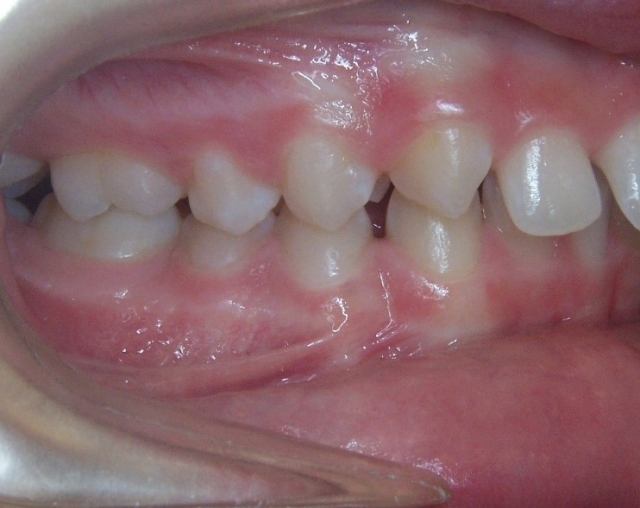

Monitoring the erupting dentition can help the patient receive the correct timing for intervention. A panoramic image as a screening procedure can confirm if there is adequate space for full permanent tooth eruption, if the eruption sequence is normal and if there are any impediments to eruption present. In Class II growth patterns in particular, noting the time for eruption of the upper second molar can make a difference in the ease of establishing the Class I molar relationship. Using methods to increase the arch length by distalizing the upper first molar can provide the dual benefit for adequate eruption space and the molar correction. (Fig. 2 and 3)

The arch width for a Class II pattern is important to note since it will play a role with both proper alignment and with proper buccal coordination of the molars. During advancement of the lower arch with growth modification, the width discrepancy between upper and lower molars will increase. The wider lower posterior molar width will advance and often result in an end-to-end buccal cusp relationship. With more severe maxillary constriction, a crossbite can result.

The arch form is also an important factor to evaluate in a Class II pattern. If the upper arch form is narrow, the upper incisors are more protrusive with an increased overjet. (Fig. 5 and 6) The maxilla appears “V” shaped from the occlusal view. (Fig. 7 and 8) The lower arch form is often broader because it is set more posterior in a wider area of the upper arch. If the full upper arch form is not expanded, there will be an excess overjet that remains. Imagine trying to align a round circle into the peak of a triangle. If the full arch is expanded with an expander, the upper and lower arches can coordinate to a normal overjet. (Fig. 4)